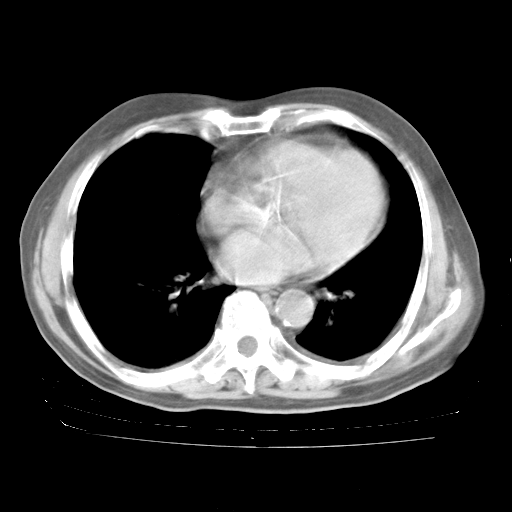

4月28日肺部CT——再次出现类似去年5月9日——磨玻璃样、间有“粟粒样”改变。